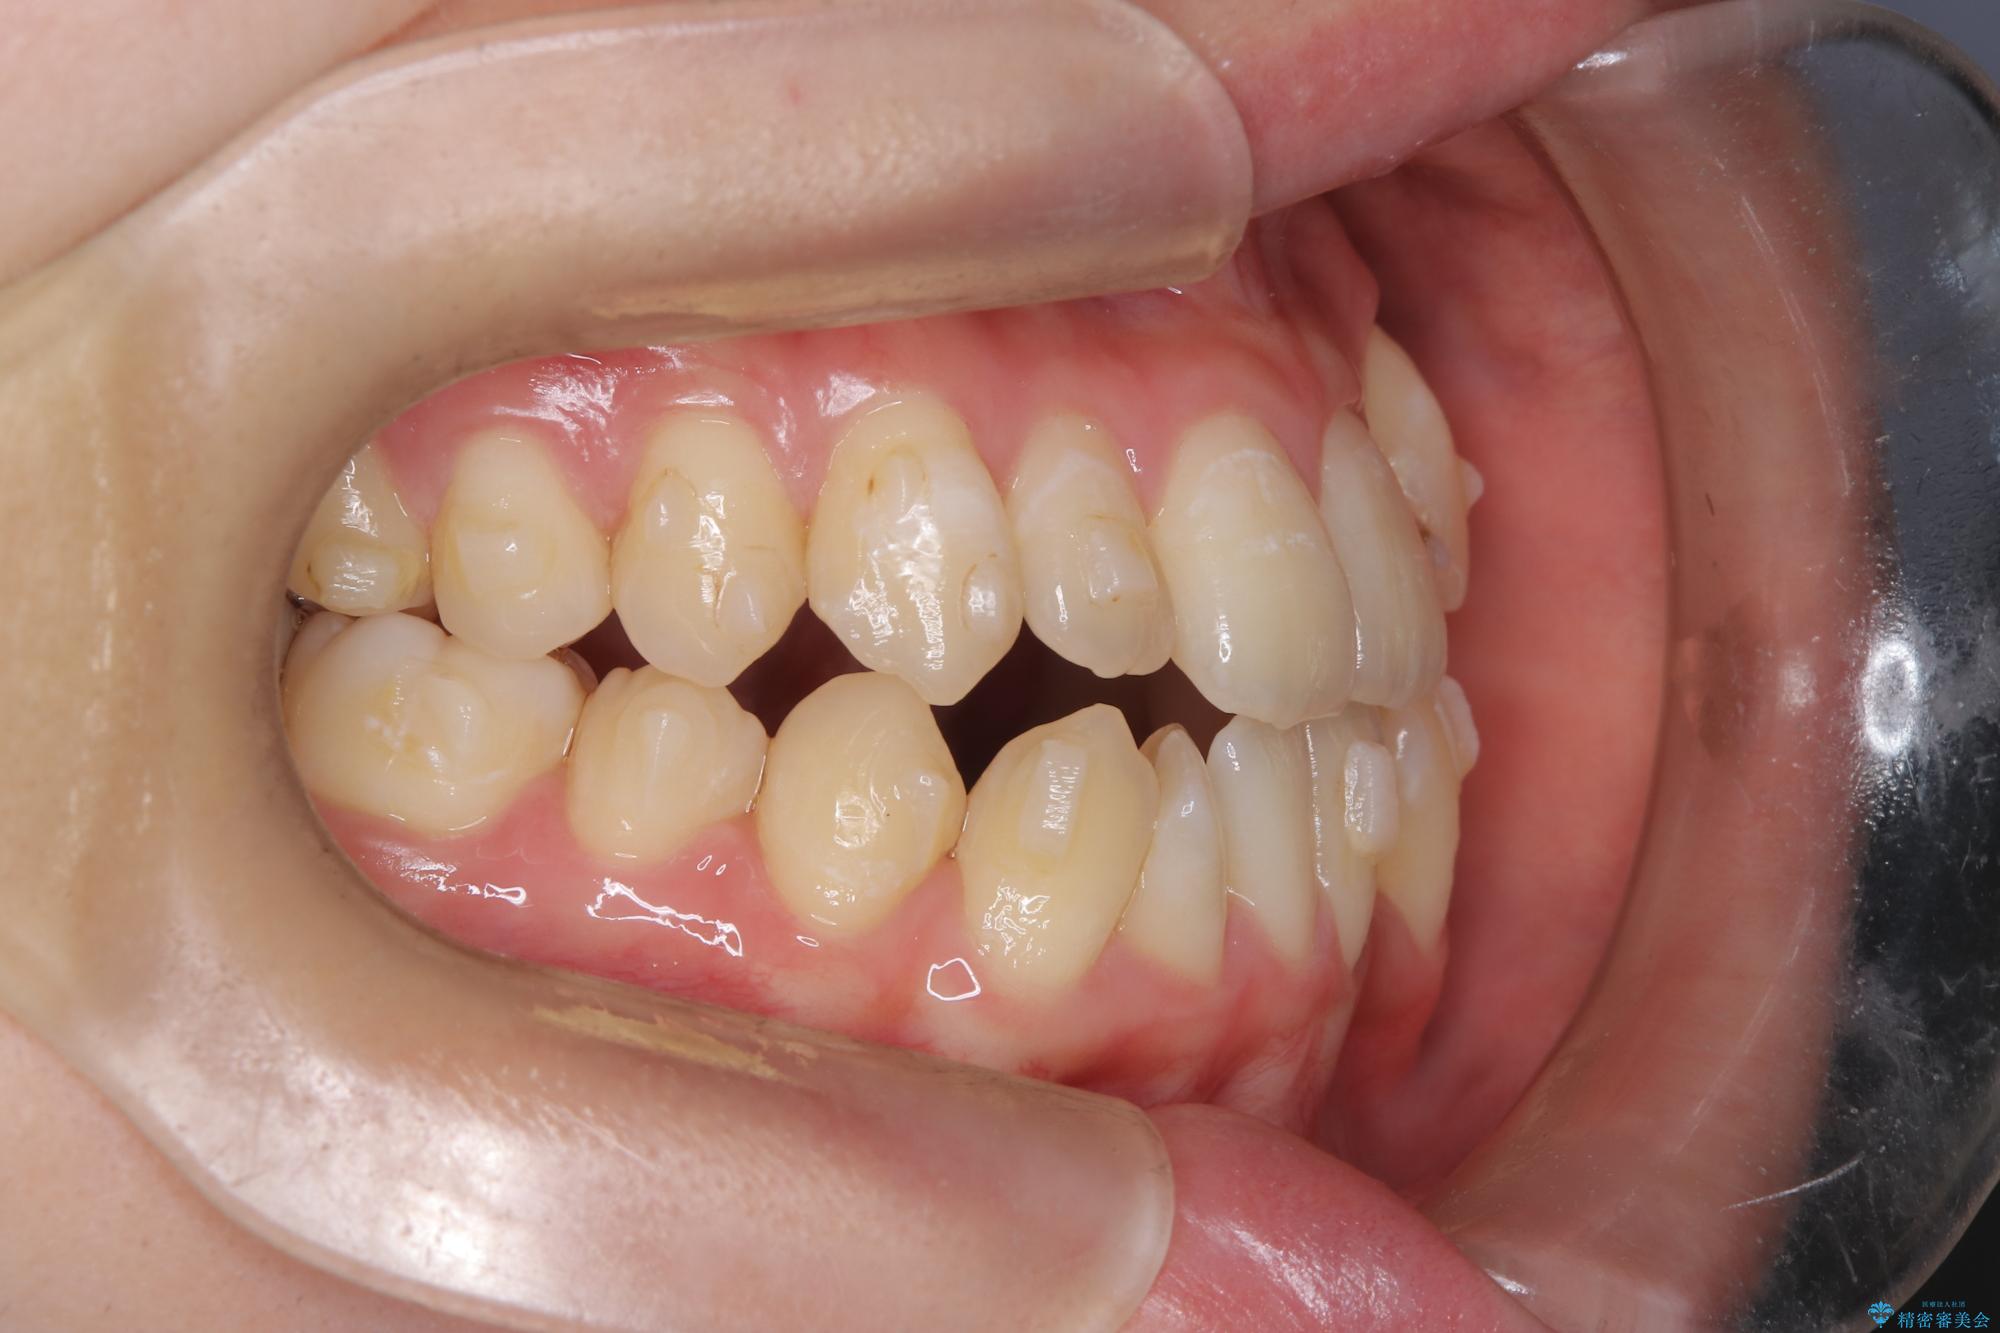

診査の結果、すでに下顎前歯の抜歯が行われていましたが、マウスピースの適合が著しく悪くなっており、歯が計画通りに動いていない状態でした。また、歯を支える骨の厚みや歯肉の薄さを考慮すると、このままマウスピースによる傾斜移動を続けるのは歯肉退縮(歯茎が下がること)のリスクが非常に高いと判断。

装置の変更と歯肉への配慮: ワイヤー矯正は歯の根(歯根)を平行に移動させる「歯体移動」を得意としています。本症例では、歯肉退縮を防ぐために、歯の傾きを精密にコントロールしながら抜歯スペースを閉じる必要がありました。ワイヤー装置を用いることで、インビザラインでは難しくなっていた三次元的な細かい調整を可能にしました。